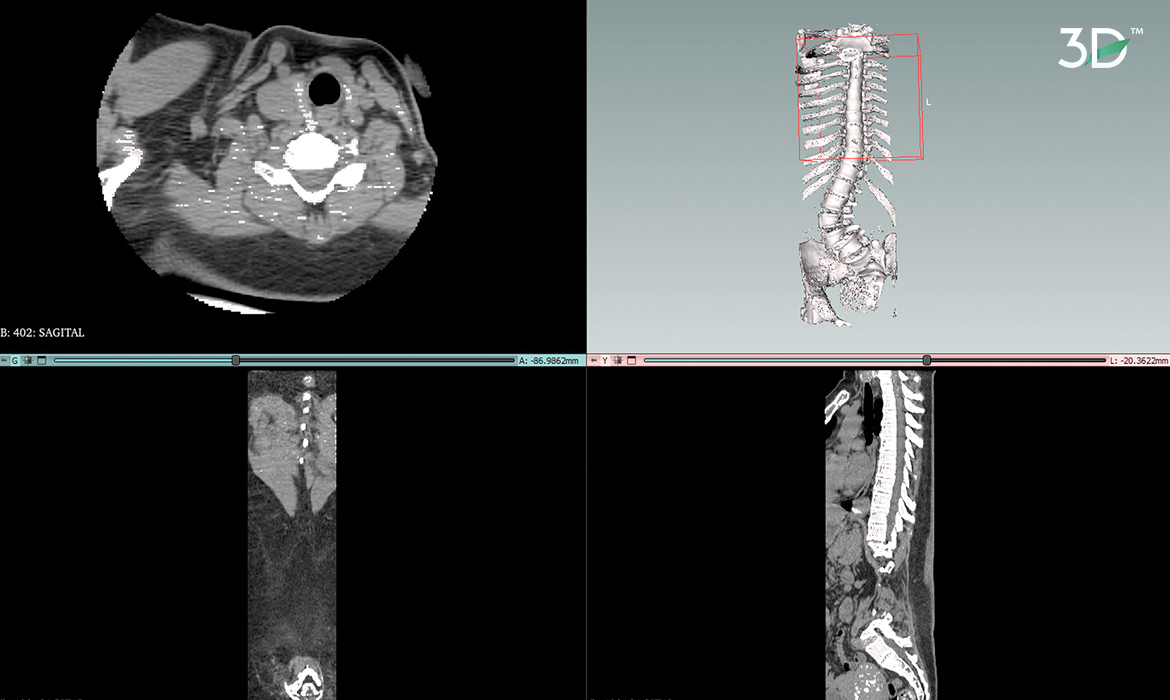

El punto de partida fue la traducción de imágenes médicas mediante la segmentación de una tomografía, lo que permitió la creación de un biomodelo 3D. Sin embargo, no bastaba con tener una réplica tridimensional; era esencial conservar los detalles anatómicos propios de la columna. Por ello, se llevó a cabo una retopología, garantizando la precisión y fidelidad del modelo. Una vez obtenido el biomodelo 3D con los detalles anatómicos adecuados, se procedió a dividir específicamente la sección de la columna que se requería imprimir. Esta sección abarcaba las áreas afectadas por la escoliosis degenerativa del adulto. Una comprensión estereoscópica a gran escala de la patología permite una planificación y una simulación más detalladas del procedimiento.